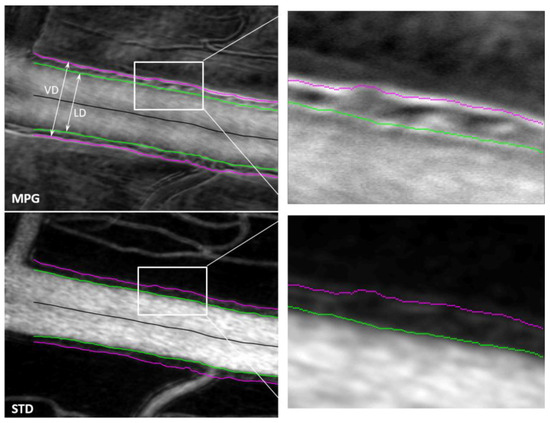

Two orthogonal split-detector images are used to calculate the magnitude of the phase gradient, which highlights local variations in the refractive index. The gradient maxima indicate the location of structural changes (edges) associated with the blood vessel wall boundaries. STD images highlight the blood flow through motion contrast, and the edges of the flow shown in these images correspond to the lumen boundaries. Segmentation of the gradient maxima and of the STD images provides the inside and outside boundaries of the vessel walls, as illustrated in Figure 4, and enables calculation of the wall-to-lumen ratio (WLR) and of other structural characteristics of the retinal vasculature.

Figure 4.

MPG (top) and STD (bottom) images with segmented vessel walls (magenta and green). The right-side column shows a magnified view of the white rectangle area in the left-side images. (VD—vessel diameter; LD—lumen diameter).

An example of the measured images (offset images im 1–4 and SLO) and derived images (split 1–4, SD, sum) is shown in Figure 5 with the blood vessel boundaries segmented and highlighted with magenta (vessel boundary on the outside) and green (lumen boundary on the inside). Figure 6A shows the vessel (VD—magenta) and the lumen (LD—green) diameters as a function of the position along the vessel. WLR is calculated as and is shown in Figure 6B. VD and LD are measured in µm; WLR is adimensional; and the horizontal axis in both plots represents the position along the vessel in µm.

Various retinal structures have a different refractive index than the tissue surrounding them. Minute variations with respect to the surroundings generate little contrast and render the structures basically transparent in transmission or hard to see in reflection. Phase imaging is sensitive to such small refractive index variations and provides additional contrast to image such structures, sometimes called phase objects. Phase gradients can be used to identify the borders of phase objects, which represent the location where the refractive index has the largest jump. Quad imaging, as presented here with two orthogonal split detection directions, can be used to calculate MPG, which highlights local variations in the refractive index. The gradient maxima indicate the location of the structural changes (edges) associated with the blood vessel wall boundaries, as shown in Figure 4. STD images highlight the blood flow through motion contrast and the edges of the flow shown in these images correspond to the lumen boundaries. Segmentation of the gradient maxima and of the STD images provides the inside (green in Figure 4 and Figure 5) and outside (magenta) boundaries of the vessel walls and enables the calculation of VD, LD, WLR, and of other structural characteristics of the retinal vasculature that have diagnostic value.

Segmentation of the MPG and STD images is currently performed semi-automatically using a custom-made Matlab program that identifies the gradient maxima in the MPG image and the borders of the flow in the STD image. Some gradient maxima such as the borders of the mural cells within the vessel wall, as can be seen in the top right image in Figure 4, are then removed manually by an expert grader (MM). Discontinuities of the identified wall boundaries are also corrected manually. The inside border of the wall is segmented simultaneously in the MPG and STD images, and the right column in Figure 4 shows a good correlation between the edge of the flow in the STD image with the gradient maxima in the MPG image, both in green. The outside border of the wall can only be segmented in the MPG image since there is no blood flow at that location to create motion contrast.

The MPG and STD images were chosen for wall segmentation because they are isotropic, independent of the offset/split direction since they were derived from all four offset/split images. SD, SLO, and sum are also isotropic, as illustrated in Figure 5. However, the wall boundaries are not visible at all in the confocal/SLO image, sum has low contrast at the borders, and SD is very similar to MPG. In addition, individual offsets and splits are not useful for vessel segmentation since the appearance of the vessel wall varies with the orientation of the vessel with respect to the image. One side of the vessel might show white boundaries, while the other side might show dark boundaries and border identification becomes very difficult. If the vessel is oriented along the offset/split direction, the boundary is lost, as illustrated in Figure 3, and cannot be segmented. MPG and STD images are the most reliable for vessel segmentation.